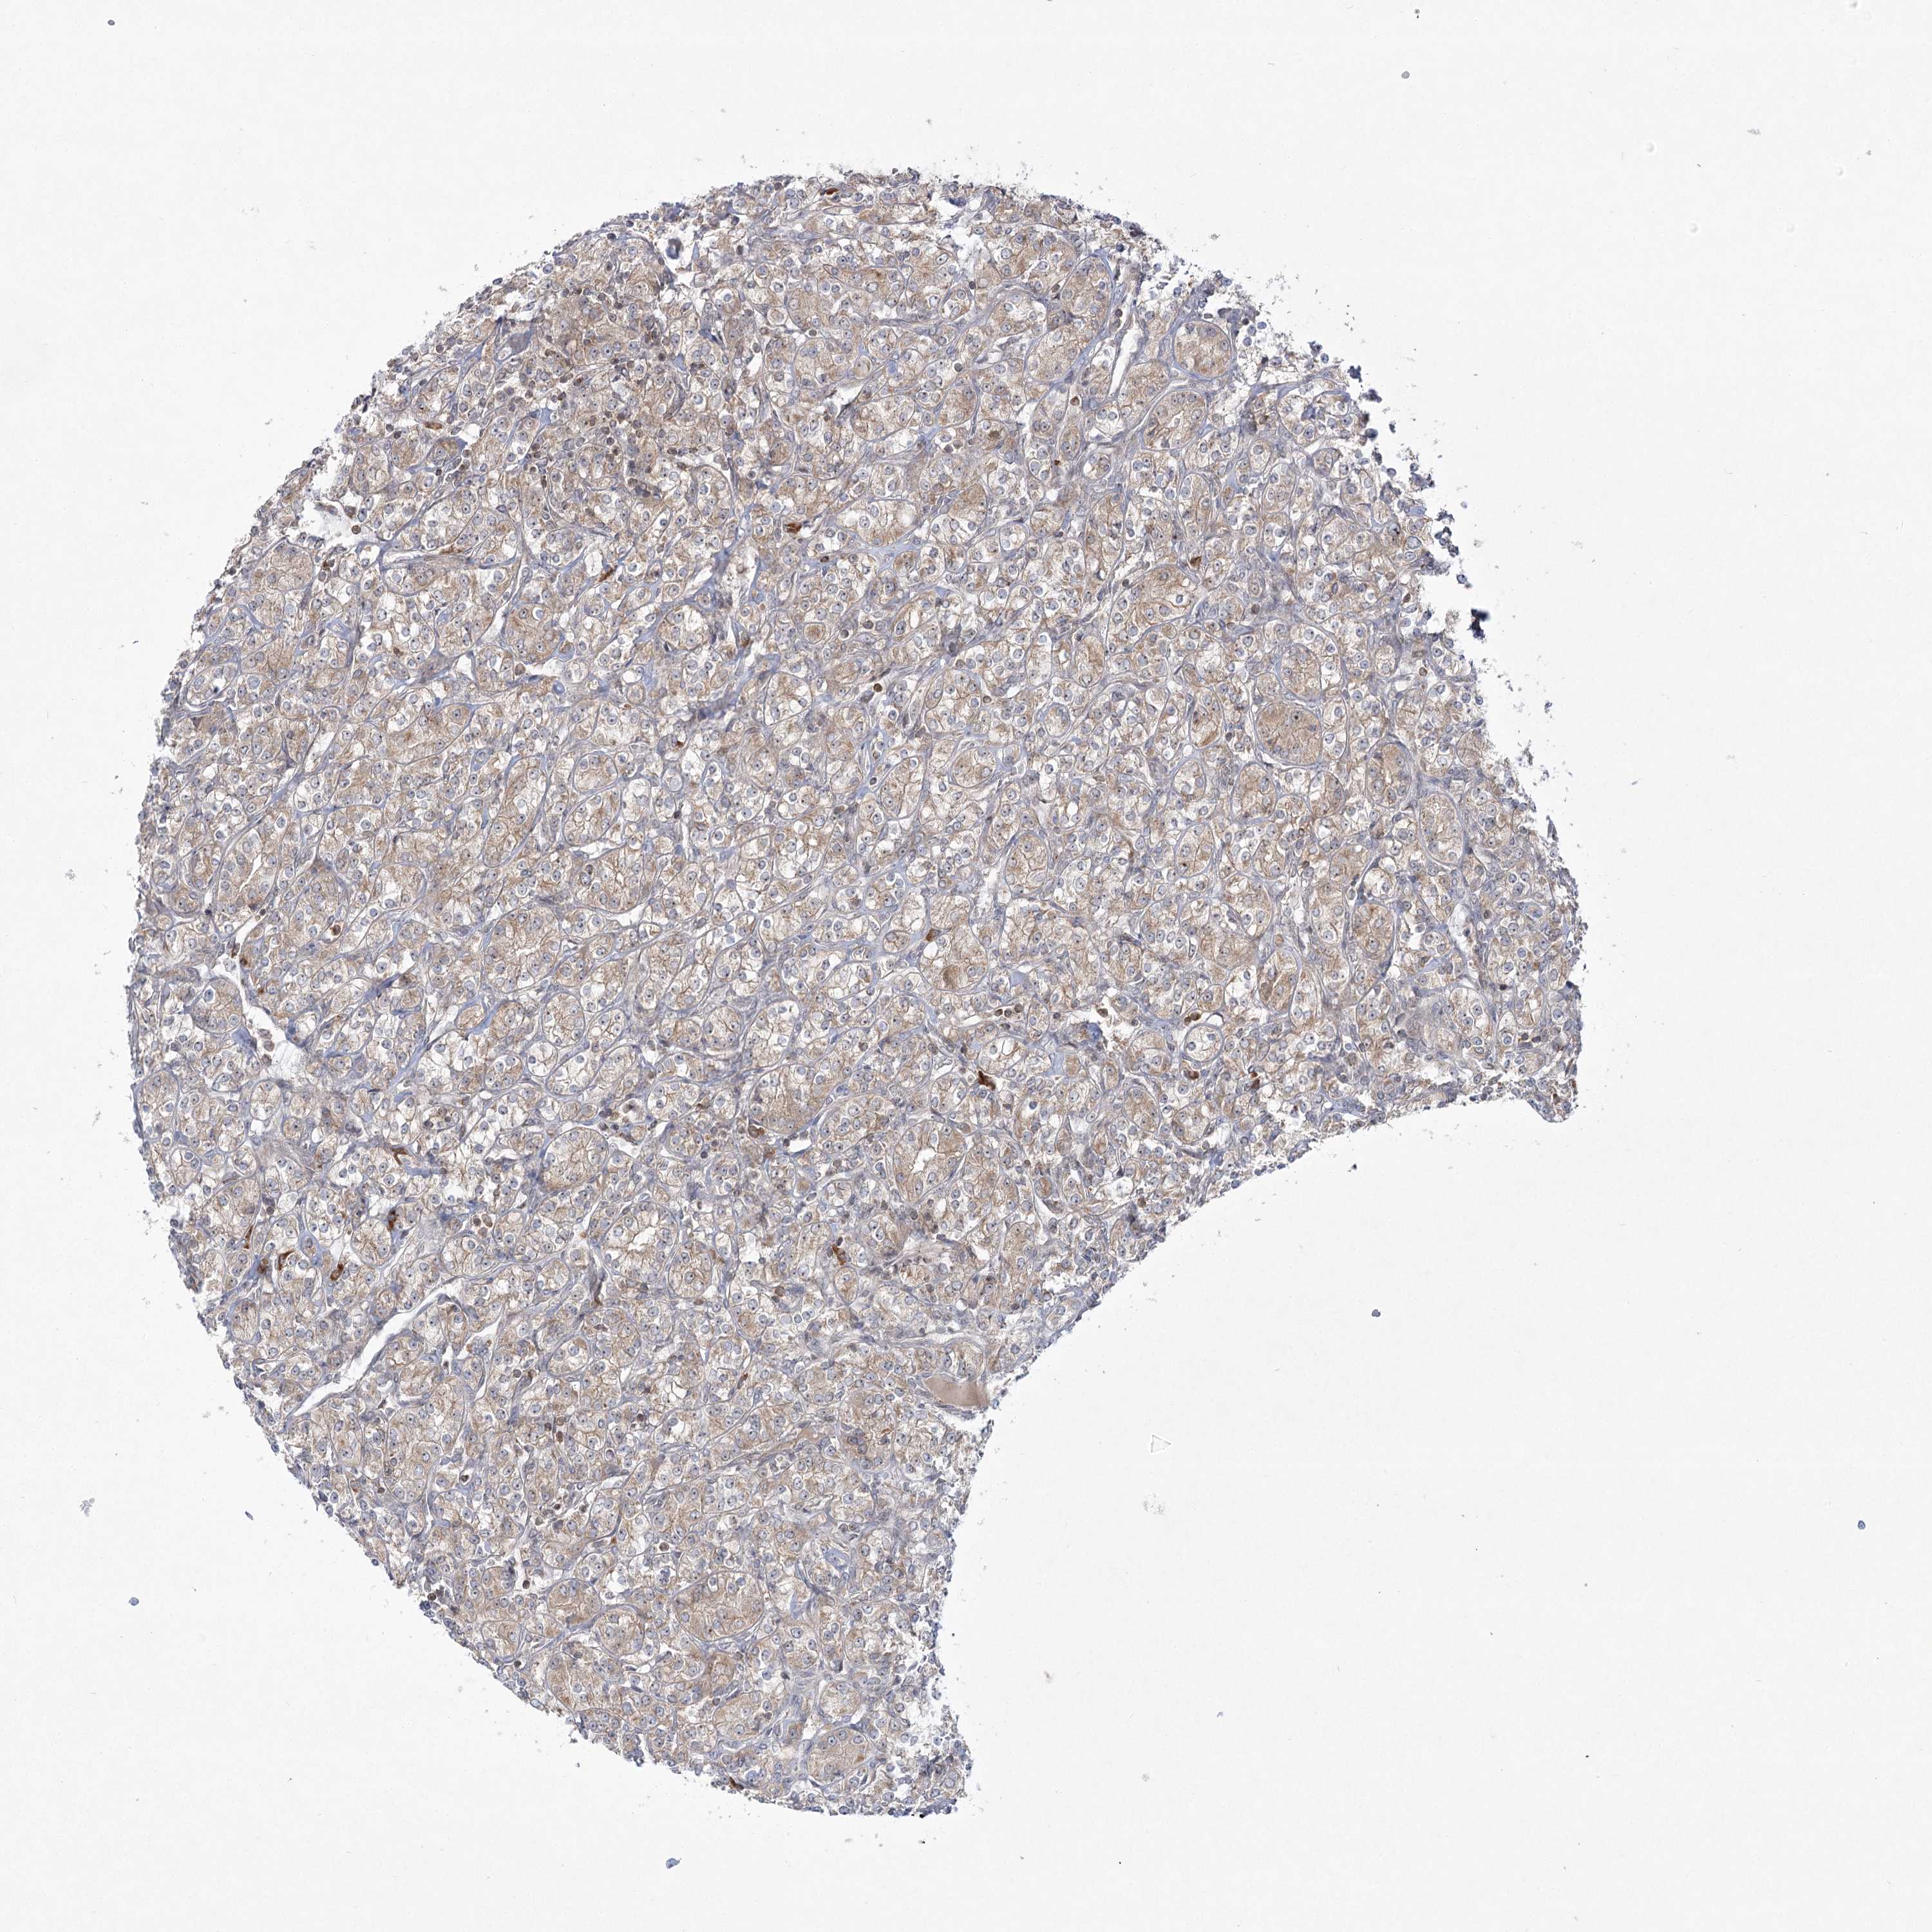

KIDNEY RENAL CLEAR CELL CARCINOMA (TCGA) - Interactive survival scatter ploti

The Survival Scatter plot shows the clinical status (i.e. dead or alive) for all individuals in the patient cohort, based on the same data that underlies the corresponding Kaplan-Meier plots. Patients that are alive at last time for follow-up are shown in blue and patients who have died during the study are shown in red.

The x-axis shows the expression levels (FPKM) of the investigated gene in the tumor tissue at the time of diagnosis. The y-axis shows the follow-up time after diagnosis (years). Both axes are complimented with kernel density curves demonstrating the data density over the axes. The top density plot shows the expression levels (FPKM) distribution among dead (red) and alive patients (blue). The right density plot shows the data density of the survived years of dead patients with high and low expression levels respectively, stratified using the cutoff indicated by the vertical dashed line through the Survival Scatter plot. This cutoff is automatically defined based on the FPKM cutoff that minimizes the p-score. The cutoff can be changed by dragging the vertical line or by entering a cutoff value in the square labeled "Current cut-off".

Under the Survival Scatter plot the p-score landscape (black curve; left axis) is shown together with dead median separation (red curve; right axis). Dead median separation is the difference in median mRNA expression between patients who have died with high and low expression, respectively. It is calculated as follows: median FPKM expression of dead patients with high expression - median FPKM expression of dead patients with low expression. This is intended to aid the user in visually exploring custom cutoffs and the associated p-scores and dead median separation.

Individual patient data is displayed and can be filtered by clicking on one or more of the category buttons on the top of the page. Categories describing expression level and patient information include: high, low, alive, dead, female, male and tumor stages. The scale of the x-axis can be toggled between linear and log-scale by clicking on the "x log" button. Mouse-over function shows TCGA ID, patient information and mRNA expression (FPKM) for each patient.

& Survival analysisi

Kaplan-Meier plots summarize results from analysis of correlation between mRNA expression level and patient survival. Patients were divided based on level of expression into one of the two groups "low" (under cut off) or "high" (over cut off). X-axis shows time for survival (years) and y-axis shows the probability of survival, where 1.0 corresponds to 100 percent.

SYTL1 is not prognostic in Kidney Renal Clear Cell Carcinoma (TCGA)

: 3.18

Average pTPM 2.6

Number of samples 521